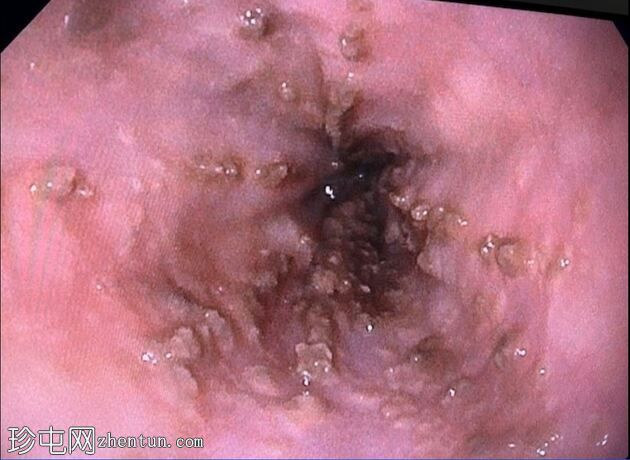

消化道内镜检查

8.jpeg

照片

十二指肠壁溃疡

9.jpeg

食管炎

止血

及止血夹

胃底可见变质血液

内镜报告:

食管:LA C级食管炎。

胃:胃底可见变质血液及大血块。吸痰、冲洗并调整患者体位以移动血块后,未在胃底或胃体部发现病变。未发现活动性出血点。

胃窦:幽门前区可见三处溃疡,每处均小于1厘米,底部均清洁。

十二指肠:

D1:D1前壁可见一处含血块的溃疡。应用两个止血夹止血,并在溃疡周围注射1:10,000肾上腺素。

D2:D2可见两处溃疡。